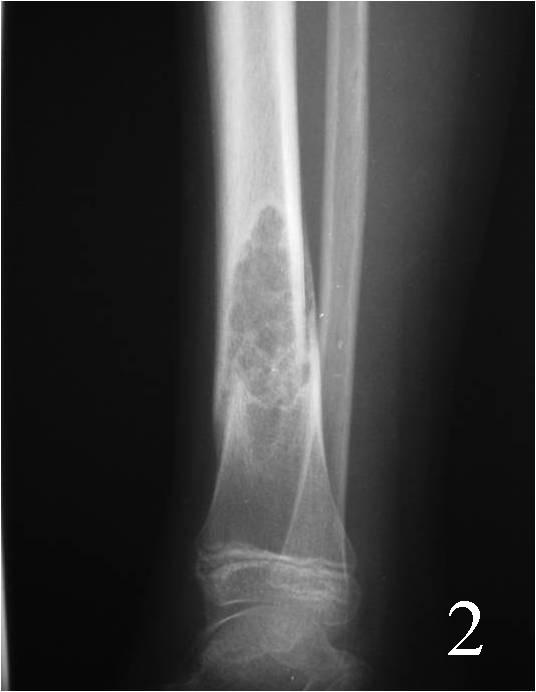

• Lytic and irregular; Well circumscribed lesion with surrounding sclerosis (fig 1-3).

• Lesions are metaphyseal and eccentric arising from or involving the cortex

• May appear expansile and sharply marginated with sclerotic rim

• The long axis of the lesion usually runs parallels to the affected bone

• Often has reactive internal trabeculations

Fig. 2

Fig. 1-2: AP (Fig. 1) and lat (Fig. 2) plain x-ray of the distal tibia-fibula shows a nonossifying fibroma of the distal tibia with a nondisplaced pathologic fracture. The lesion is geographic, well circumscribed, lytic, eccentric, arising in the metaphysis and has internal trabeculations. There is a sclerotic margin.